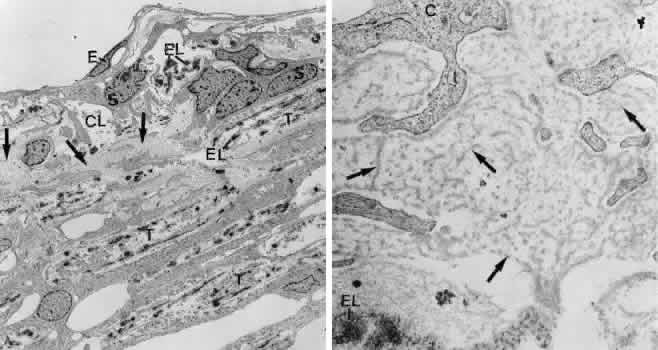

The mechanism of pressure elevation in corticosteroid-induced glaucoma is also not understood. In trabeculectomy specimens and in donor eyes treated with corticosteroids for various time periods,106 accumulation of extracellular material distinct from the sheath-derived plaques typical for POAG and from pseudoexfoliative material was observed.104–106 Directly beneath the inner wall endothelium, an accumulation of densely packed fine fibrils was seen. At places these fibrils separated the connecting fibrils from the inner wall endothelium (Fig. 35).106 In the cribriform meshwork, fingerprint-like arranged material resembling basement membranes was found.104,106

Fig. 35. Electron micrographs of the trabecular meshwork in a case of corticosteroid glaucoma in a 63-year-old woman. A. Survey figure showing the cribriform layer (CL) and the adjacent corneoscleral lamellae (T). Deposits of extracellular material, typical for corticosteroid glaucoma, are indicated by arrows (× 5,000). E, endothelium of Schlemm's ca-nal; EL, elastic-like fibers; S, subendothelialcells of the cribriform layer. B. Higher magni-fication of the cribriform layer showing thedeposits of extracellular material, characteris-tic for corticosteroid glaucoma (arrows)(× 51,000). C, cells of cribriform layer; EL, elastic-like fiber.